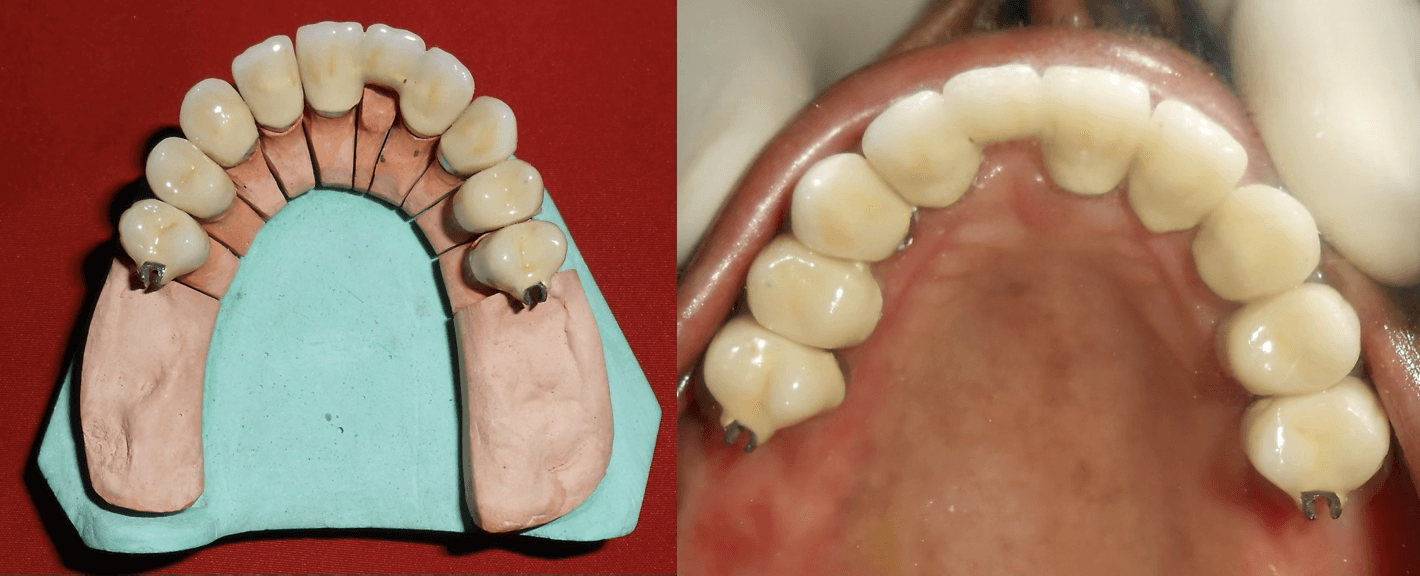

Precision-attached metal framework fabricated and tested. Custom teeth arrangement trial to ensure optimal function and appearance.

Implants were delayed loaded after 3 months with PFM crowns. Precision-attached metal removable denture was inserted for comprehensive hemimandibulectomy rehabilitation.